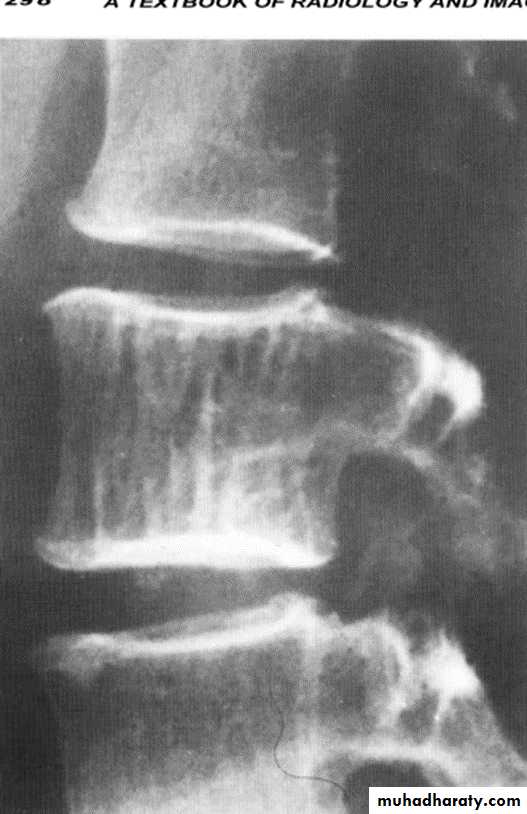

Haemangioma of the vertebral body of L3.

The whole body is marked by the characteristic vertical striationThe body of thoracic v. appeared as an area of high signal intensity on T1-T2-weighted images (a and b)